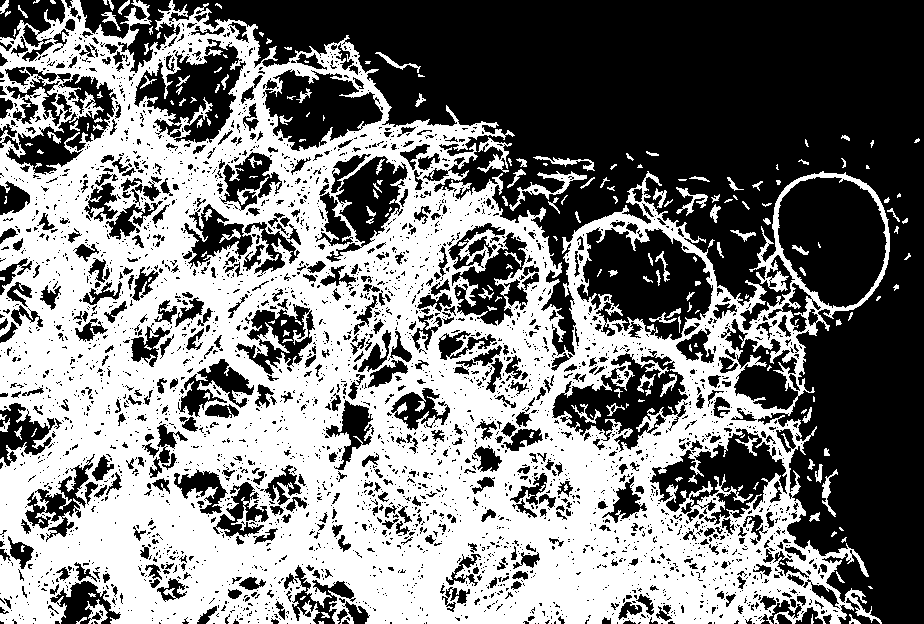

Figure 2. Images of a human glioblastoma brain tumor taken from the Ivy Glioblastoma Atlas Project (Ivy GAP).

Glioblastoma is an aggressive cancer of the supportive cells of the central nervous system. While most treatment plans for glioblastoma include surgery and radiation therapy to physically reduce the size of the tumor, the molecular basis of glioblastoma can differ widely across individual patients.

What does that mean for the patient? The heterogeneity of molecular markers across glioblastoma cases means that oncologists—and patients—spend time on diagnostics that could be spent in treatment. The Ivy Glioblastoma Atlas Project (Ivy GAP) aimed to reduce that time by characterizing over 40 glioblastoma samples at the molecular and genetic level. Each image has been annotated for tumor features by a machine learning (ML) process trained by medical experts. Ivy GAP is accompanied by a patient genomic and clinical database which users can register for and request access to, as well as RNA sequencing of each tumor. Ivy GAP gives researchers around the world a foundational resource for exploring the anatomic and genetic basis of glioblastoma at the cellular and molecular levels.